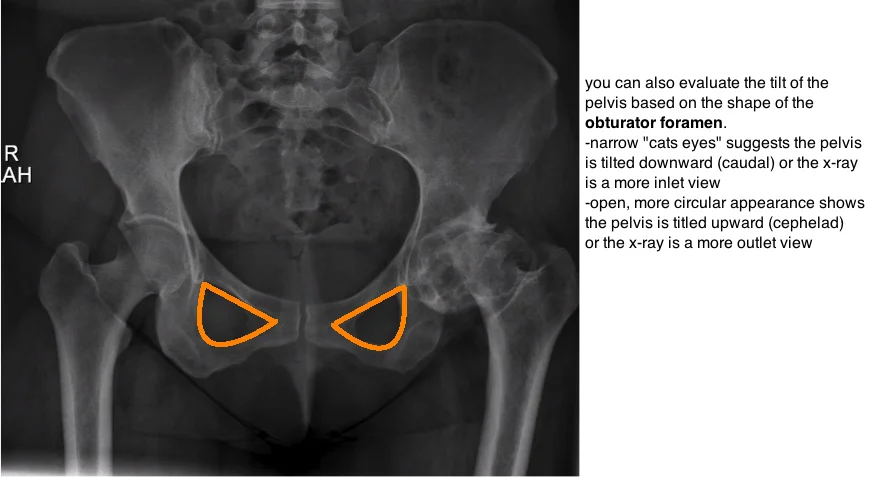

evaluating pelvic tilt on ap xray